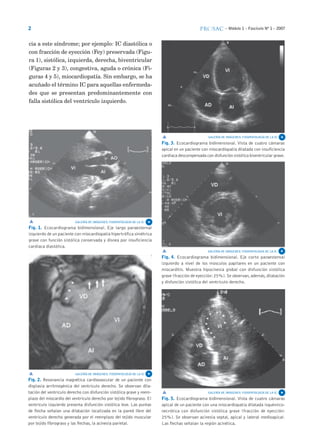

cia a este síndrome; por ejemplo: IC diastólica o

con fracción de eyección (Fey) preservada (Figu-

ra 1), sistólica, izquierda, derecha, biventricular

(Figuras 2 y 3), congestiva, aguda o crónica (Fi-

guras 4 y 5), miocardiopatía. Sin embargo, se ha

acuñado el término IC para aquellas enfermeda-

des que se presentan predominantemente con

falla sistólica del ventrículo izquierdo.

Fig. 3. Ecocardiograma bidimensional. Vista de cuatro cámaras

apical en un paciente con miocardiopatía dilatada con insuficiencia

cardíaca descompensada con disfunción sistólica biventricular grave.

Fig. 2. Resonancia magnética cardiovascular de un paciente con

displasia arritmogénica del ventrículo derecho. Se observan dila-

tación del ventrículo derecho con disfunción sistólica grave y reem-

plazo del miocardio del ventrículo derecho por tejido fibrograso. El

ventrículo izquierdo presenta disfunción sistólica leve. Las puntas

de flecha señalan una dilatación localizada en la pared libre del

ventrículo derecho generada por el reemplazo del tejido muscular

por tejido fibrograso y las flechas, la acinesia parietal.

Fig. 4. Ecocardiograma bidimensional. Eje corto paraesternal

izquierdo a nivel de los músculos papilares en un paciente con

miocarditis. Muestra hipocinesia global con disfunción sistólica

grave (fracción de eyección:25%).Se observan,además,dilatación

y disfunción sistólica del ventrículo derecho.

Fig. 5. Ecocardiograma bidimensional. Vista de cuatro cámaras

apical de un paciente con una miocardiopatía dilatada isquémico-

necrótica con disfunción sistólica grave (fracción de eyección:

25%). Se observan acinesia septal, apical y lateral medioapical.

Las flechas señalan la región acinética.